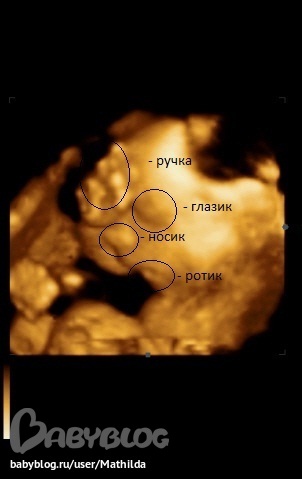

хи-хи, похожа, я тоже во 2 б. делала 3Д и тоже сходство уже с 22 нед. есть))). И в эту б. тоже буду 3Д делать. А рядом со лбом ладошка на узи?

очень похожа) носик, губки)) здорово)) а мне на 3Д узи показалось что малышка на папу похожа, видимо так и будет))

очень похожа))) прям точь в точь))) даже нижнюю губку так же держит)))

меня вообще 3д узи пугает)))))не детки а монстры какие-то получаются на фото)

подруга в подарок подарила 3Д-УЗИ))) Классная штука))))